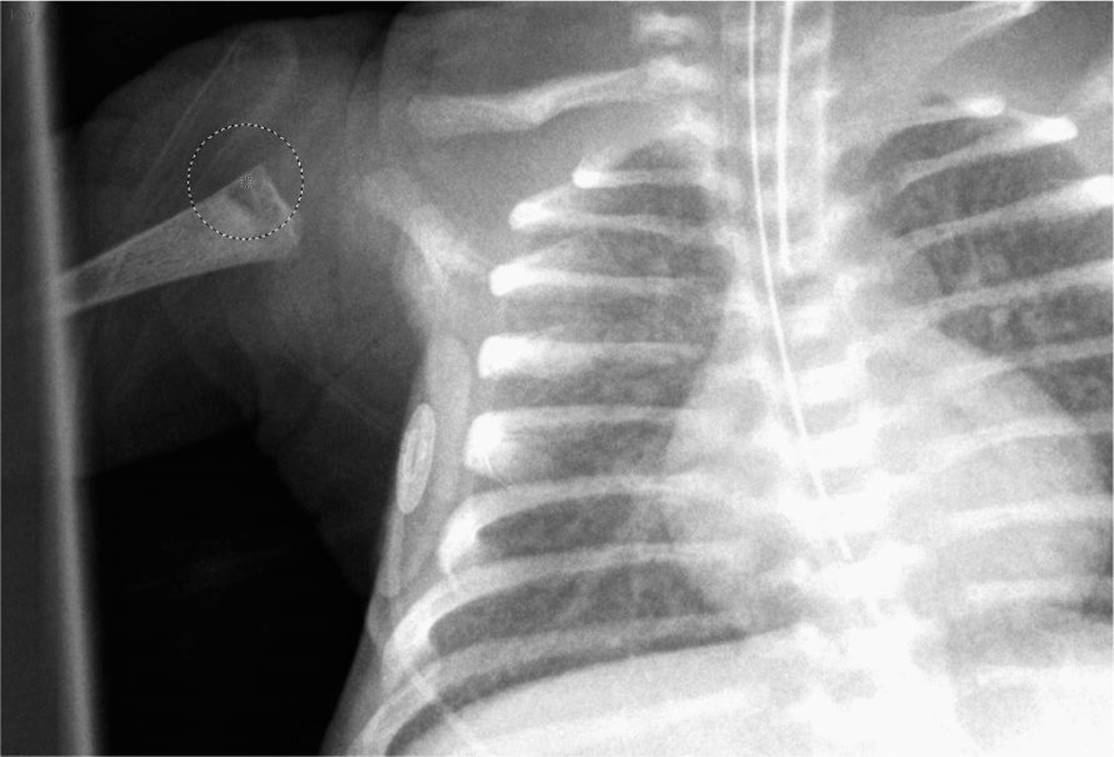

During the assessment, a rash noted on the mothers hands strongly suggested the infant’s diagnosis (Figure 15-1). Radiographs of the infant’s humerus (Figure 15-2) and femur (Figure 15-3) were also consistent with the diagnosis. The infant was admitted to the neonatal intensive care unit for additional diagnostic testing and treatment.

FIGURE 15-2. There are areas of metaphyseal lucency in the proximal humerus.

The mothers’ hand revealed a pink, elliptical macules (Figure 15-1); the central area was darker than the periphery, which blended into the surrounding skin. The reddish hue, due to localized hyperemia, is characteristic of early secondary syphilis. Laboratory testing was significant for an RPR of 1:8 in the mother and 1:64 in the baby. These positive tests were confirmed with a positive Treponema pallidumparticle agglutination (TP-PA) assay. The infant received a lumbar puncture to evaluate for neurosyphilis. CSF protein and cell count were normal and CSF Venereal Disease Research Laboratory (VDRL) test was 1:8. She had a liver ultrasound that showed a homogenous enlarged liver and spleen with a normal gallbladder. The chest radiograph was normal. However, long-bone radiographs revealed metaphyseal lucencies involving the proximal humerus (Figure 15-2) and femur (Figure 15-3) that were consistent with the diagnosis of congenital syphilis. Testing for other TORCH infections as well as hepatitis B and C and HIV was negative. Given the presence of a positive RPR and TP-PA in both the mother and baby, in conjunction with the clinical findings of lymphadenopathy, jaundice, hepatosplenomegaly, and metaphyseal dystrophy, the patient was diagnosed with congenital syphilis.

The infant displayed many of the clinical features consistent with early congenital syphilis, including jaundice, hepatosplenomegaly, thrombocytopenia, rash, “snuffles,” pseudoparalysis, and metaphyseal dystrophy of the humerus and femur.